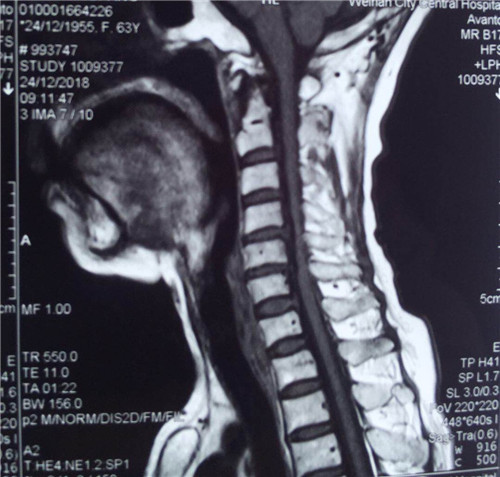

术前

患者入院后,骨一科医护人员为其做进一步检查,诊断为多发颈椎间盘突出并继发颈椎管狭窄症。经讨论研究后,程福宏副主任医师决定为其行颈后路颈4、5、6的单开门椎板扩大成形术,该手术在王小峰主治医师的配合下完成。术中,医生为患者进行彻底的减压脊髓,固定椎板。术后患者恢复较好,症状改善明显,已能够独自行走,恢复正常活动。